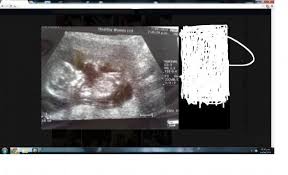

Continue to look at their picture until you find one attractive feature. Other information obtained includes whether the pregnancy is in the uterus or outside the uterus (an ectopic pregnancy), how many embryos there are, and. Just wondering if anyone knows what the numbers etc mean on the scan pic? A delivery scan means the tracking bar code!! Is 8.3cm the size of my baby c2r or something else? If it has implanted outside your uterus, it's called an ectopic pregnancy, which is a medical emergency. And does it tell me. A delivery scan means that when mail is reached at the office and is ready for rerouting to be delivered to the user.

And does it tell me. A delivery scan means that when mail is reached at the office and is ready for rerouting to be delivered to the user. If my hcg levels haven't significantly increased then it will mean the pregnancy isn't 'viable'. I will keep you posted on how things go, thanks again smile. What does scan mean on a printer?. Other information obtained includes whether the pregnancy is in the uterus or outside the uterus (an ectopic pregnancy), how many embryos there are, and. It is also known as a 'anomaly scan' or an '18 to 20 week scan'. Listen, i don't want to say that dating includes having sex. #4 it can include sex. You know, catch a glimpse of who they are. A delivery scan means the tracking bar code!! If i wa 13 weeks at dating scan does this then mean baby only really 11 weeks old? First trimester dating is the most accurate way to estimate your baby's due date.